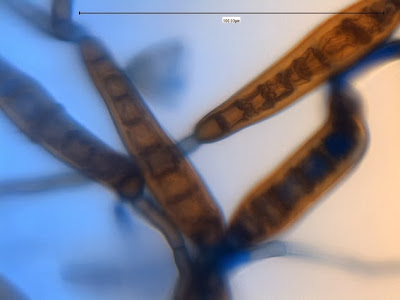

Hyphae are septate and darken with the development of melanin. Conidiophores are rather long (up to 200 - 230 µm in length, 5 – 8 µm wide) and are also septate. Conidiophores exhibit sympodial geniculate growth, where conidia are produced at bends (geniculate) as the conidiophore extends. This gives the conidiophore a knobby, zigzag appearance where the conidia attach. The mature conidia (ave. 14 X 80 µm or greater) are straight to slightly curved and are fusiform or ellipsoidal in shape with rather smooth walls. Conidia are compartmentalized with between 7 to 11 septa and has a distinctive protruding dark hilum (scar) at the base where once attached.More specifically, the conidia are ‘poroconidia’, a distinction where the conidia are produced through the extrusion or extension of the inner walls of the conidiogenous cells through a pore or channel.

Exserohilum rostratum - Large, compartmentalized conida which are somewhat fusiform in appearance and may appear slightly bent or curved. (400X, LPCB, DMD-108)

Exserohilum rostratum - as above. Showing variation in size and shape of conidia. Brown pigmentation due to the production and accumulation of melanin. (400X, LPCB, DMD-108)